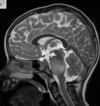

Q

A

Esclerose mesial temporal

Observe a perda de volume, que indica atrofia e causa aumento secundário do corno temporal do ventrículo lateral.

O sinal alto no hipocampo reflete a gliose.

How well did you know this?

Qual o padrão da Esclerose mesial temporal?

Atrofia hipocampal e hipersinal T2. Cerca de 10% dos casos são bilaterais (dificulta o diagnóstico). A etiologia é desconhecida, mas há uma relação entre STM e convulsões febris prolongadas no início da vida A esclerose mesial temporal pode ocorrer em associação com outras patologias, principalmente displasia cortical focal (dual pathology).